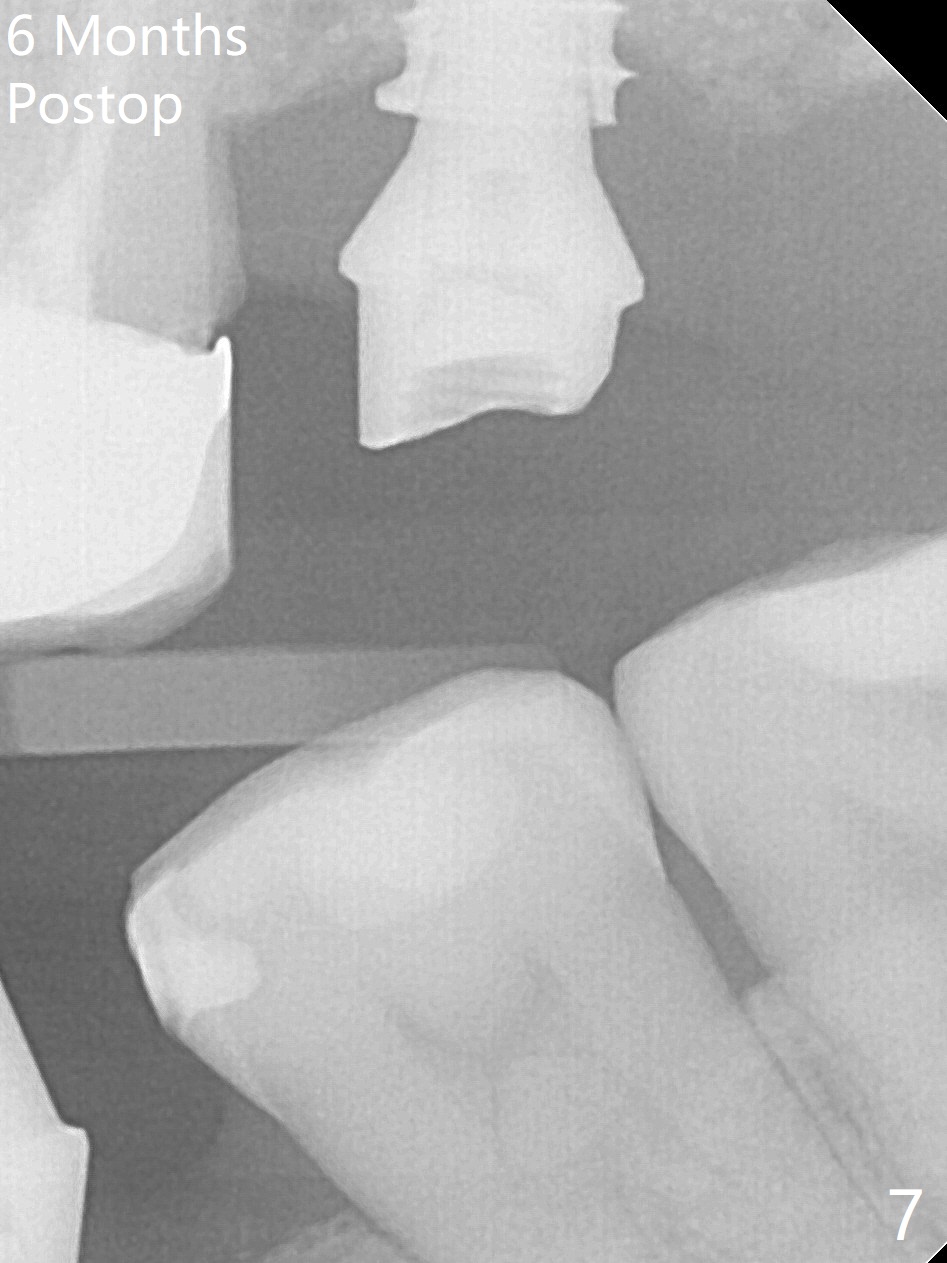

After removal of the mesial (M) and distal (D) residual roots of the tooth #15 (Fig.1,2), Magic Split is used to test bone density (high), followed by Magic Drills from Magic Sinus Lift Kit (for 4 mm) and Magic Surgical Kit (for 5 mm). It appears that the sinus floor has been perforated with the intact sinus membrane. Following minimal use of Magic Lifter, Vanilla Graft is inserted (Fig.3,4 *) and a 4x9 mm dummy implant is placed. After placement of more allograft (Fig.5 *), a 5x7 mm implant is placed with ~ 35 Ncm. With placement of a 5.5x4(2) mm abutment, an immediate provisional is fabricated to close the socket. Six months postop, the bone graft remains in the sinus around the apical end of the implant (Fig.6 *), while there seems no bone loss coronally (Fig.7). In fact there is, as shown later (Fig.8-11 < and lingual (L)). The crown is recemented 6 months post cementation (due to short abutment). The abutment seems to be incompletely seated. When the crown at #14 is reprep following #13 implant, the abutment screw is being untightened, the crown dislodges first. The abutment is confirmed short with more than enough occlusal clearance. After use of 5.5 and 6.0 mm bone profile drills, a 5x4(3) mm abutment is placed with complete seating.